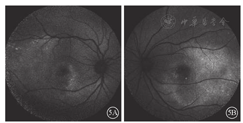

患者女,26岁。因左眼视物变形1个月于2018年9月17日到上海和平眼科医院就诊。患者3年前于外院诊断为"双眼闭角型青光眼",并行双眼YAG激光虹膜周边切除手术。否认家族遗传病史,其母视力及眼底检查正常,其父视力正常。10多岁时发现夜盲。患者一般情况良好。眼科检查:右眼视力1.0;左眼视力0.6,矫正不能提高。双眼屈光度均为+0.5 DS。右眼、左眼眼压分别为30、28 mmHg (1 mmHg=0.133 kPa)。双眼眼轴长度均为21 mm。双眼眼前节正常,前房浅,上方虹膜周切口通畅。晶状体透明,玻璃体不混浊。双眼视盘边界清楚,C/D为0.8;视网膜血管未见明显异常。双眼视网膜后极部不均匀黄白色物质沉积,黄斑中心凹反光消失(图1)。频域OCT (SD-OCT)检查,右眼内核层层间劈裂,外界膜下椭圆体带、光感受器外节大量强反射物质沉积,RPE/Bruch膜上锥形强反射物质沉积,两层强反射之间有弱反射暗区(空腔);左眼黄斑中心凹RPE下强反射隆起,Bruch膜断裂(图2)。OCT血管成像(OCTA)检查,右眼脉络膜毛细血管层大片血流信号遮蔽成暗区,其内及边缘见小片状非血流信号团;左眼无脉管层暗区内见线团状异常血流信号团(图3)。FFA检查,右眼黄斑中心凹旁斑片状强荧光,晚期染色;左眼晚期黄斑鼻下方三角形强荧光素渗漏(图4)。FAF检查,双眼后极部斑点状环形强荧光,累及颞侧及下方视网膜(图5)。EOG检查,双眼光峰值降低或消失,右眼、左眼Arden比值分别为1.2、1.1。诊断:双眼常染色体隐性卵黄样黄斑营养不良(ARB );左眼脉络膜新生血管(CNV)。患者于复旦大学附属眼耳鼻喉科医院行基因检测,提示BEST1基因杂合突变,突变位点c.140G> A,氨基酸变化p.R47H。给予双眼降眼压药物治疗;左眼玻璃体腔注射雷珠单抗治疗,每月1次,连续3次。左眼第1次注射后,患者诉视物变形症状消失;视力1.0。随访至今无变化。

BEST1基因相关ARB为少见眼底病变,其起源于RPE基底外侧的BEST1基因发生突变,BEST1基因失去功能,导致RPE及视网膜功能障碍[1,2,3,4,5]。该病好发于儿童及年青人,性别无异。双眼或单眼中心视力下降是主要症状。眼底检查可见黄斑区多个位于视网膜下的黄白色沉着物,可以累及血管弓周围甚至中周部视网膜。病变在FAF检查下显示更为清楚,且数量更多。OCT检查可见视网膜内囊样水肿或黄斑视网膜脱离;RPE上或内见到强反射团块即为黄白色沉着物;视网膜外层椭圆体带可能断裂,RPE也可出现萎缩。OCTA检查可见脉络膜毛细血管层血流信号被卵黄样物质遮蔽形成暗区,在无脉管层清晰显示暗区内线团状的异常血流信号团,即CNV。而FFA上因卵黄样物质染色等原因不易发现新生血管渗漏。这提示,对于ARB患者,OCTA检查更容易清楚发现CNV病灶。既往研究发现,与显性卵黄样黄斑营养不良(BEST病)的正常ERG表现有所不同,ARB患者可能有视锥、视杆细胞振幅降低或潜伏期延长[6]。但本例患者因客观原因未能行ERG检查。其EOG检查可见光峰值降低或消失。本例患者临床及多模式影像检查均符合ARB的眼底特征。